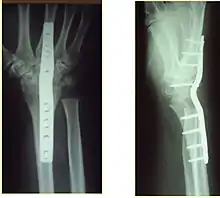

Surgery

Surgery is generally indicated for displaced or unstable fractures.[18] The techniques of surgical management include open reduction internal fixation (ORIF), external fixation, percutaneous pinning, or some combination of the above. The choice of operative treatment is often determined by the type of fracture, which can be categorized broadly into three groups: partial articular fractures, displaced articular fractures, and metaphyseal unstable extra- or minimal articular fractures.[5]

Significant advances have been made in ORIF treatments. Two newer treatments are fragment-specific fixation and fixed-angle volar plating. These attempt fixation rigid enough to allow almost immediate mobility, in an effort to minimize stiffness and improve ultimate function; no improved final outcome from early mobilization (prior to 6 weeks after surgical fixation) has been shown. Although restoration of radiocarpal alignment is thought to be of obvious importance, the exact amount of angulation, shortening, intra-articular gap/step which impact final function are not exactly known. The alignment of the DRUJ is also important, as this can be a source of a pain and loss of rotation after final healing and maximum recovery.

Little joint involvement

These fractures are the most common of the three groups mentioned above that require surgical management.[5] A minimal articular fracture involves the joint, but does not require reduction of the joint. Manipulative reduction and immobilization were thought to be appropriate for metaphyseal unstable fractures. However, several studies suggest this approach is largely ineffective in patients with high functional demand, and in this case, more stable fixation techniques should be used.[20][21][22]

Surgical options have been shown to be successful in patients with unstable extra-articular or minimal articular distal radius fractures. These options include percutaneous pinning, external fixation, and ORIF using plating. Patients with low functional demand of their wrists can be treated successfully with nonsurgical management; however, in more active and fit patients with fractures that are reducible by closed means, nonbridging external fixation is preferred, as it has less serious complications when compared to other surgical options.[5] The most common complication associated with nonbridging external fixation is pin tract infection, which can be managed with antibiotics and frequent dressing changes, and rarely results in reoperation.[5] The external fixator is placed for 5 to 6 weeks and can be removed in an outpatient setting.[5]

If the fractures are unlikely to be reduced by closed means, open reduction with internal plate fixation is preferred.[5] Although major complications (i.e. tendon injury, fracture collapse, or malunion) result in higher reoperation rates (36.5%) compared to external fixation (6%), ORIF is preferred, as this provides better stability and restoration of the volar tilt.[5][23] Following the operation, a removable splint is placed for 2 weeks, during which time patients should mobilize the wrist as tolerated.[5]